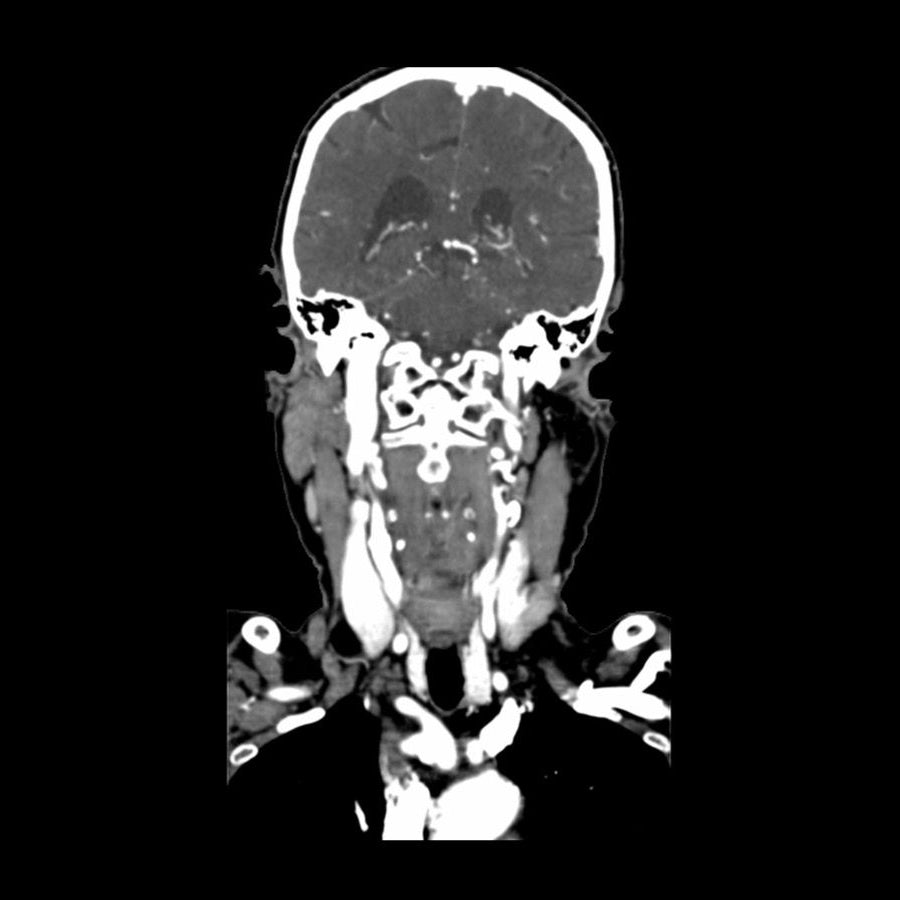

This phantom simulates a contrast medium enhanced head in arterial phase (CT angiography). The neck and upper thorax are included up to the aortic arch and the fifth thoracic vertebra. The vertex is included until approximately 0.5 cm below skin level. The thoracic phantom section excludes shoulder and back parts that are typically not part of CTA examinations. The interncal carotid artery has calcifications on both sides with moderate stenosis on the right side. Otherwise, the phantom has no significant vascular pathologies.

The phantom can be used in CT (including CBCT) to evaluate and optimize CTA imaging performance and post-processing applications such as vessel segmentation, including AI-enabled applications. It is also nicely suited for training purposes. The phantom provides a detailed and realistic simulation of vascular structures, soft and bone tissue, including small details such as lymph nodes. Air voids are filled with a cellulose-polymer composite of approx. -160 HU.

Realistic simulation of head and neck vessels up to the aortic arch, bone and soft tissues.

Calcifications of the internal carotid artery at the carotid bifurcation on both sides with mild stenosis on the right side.